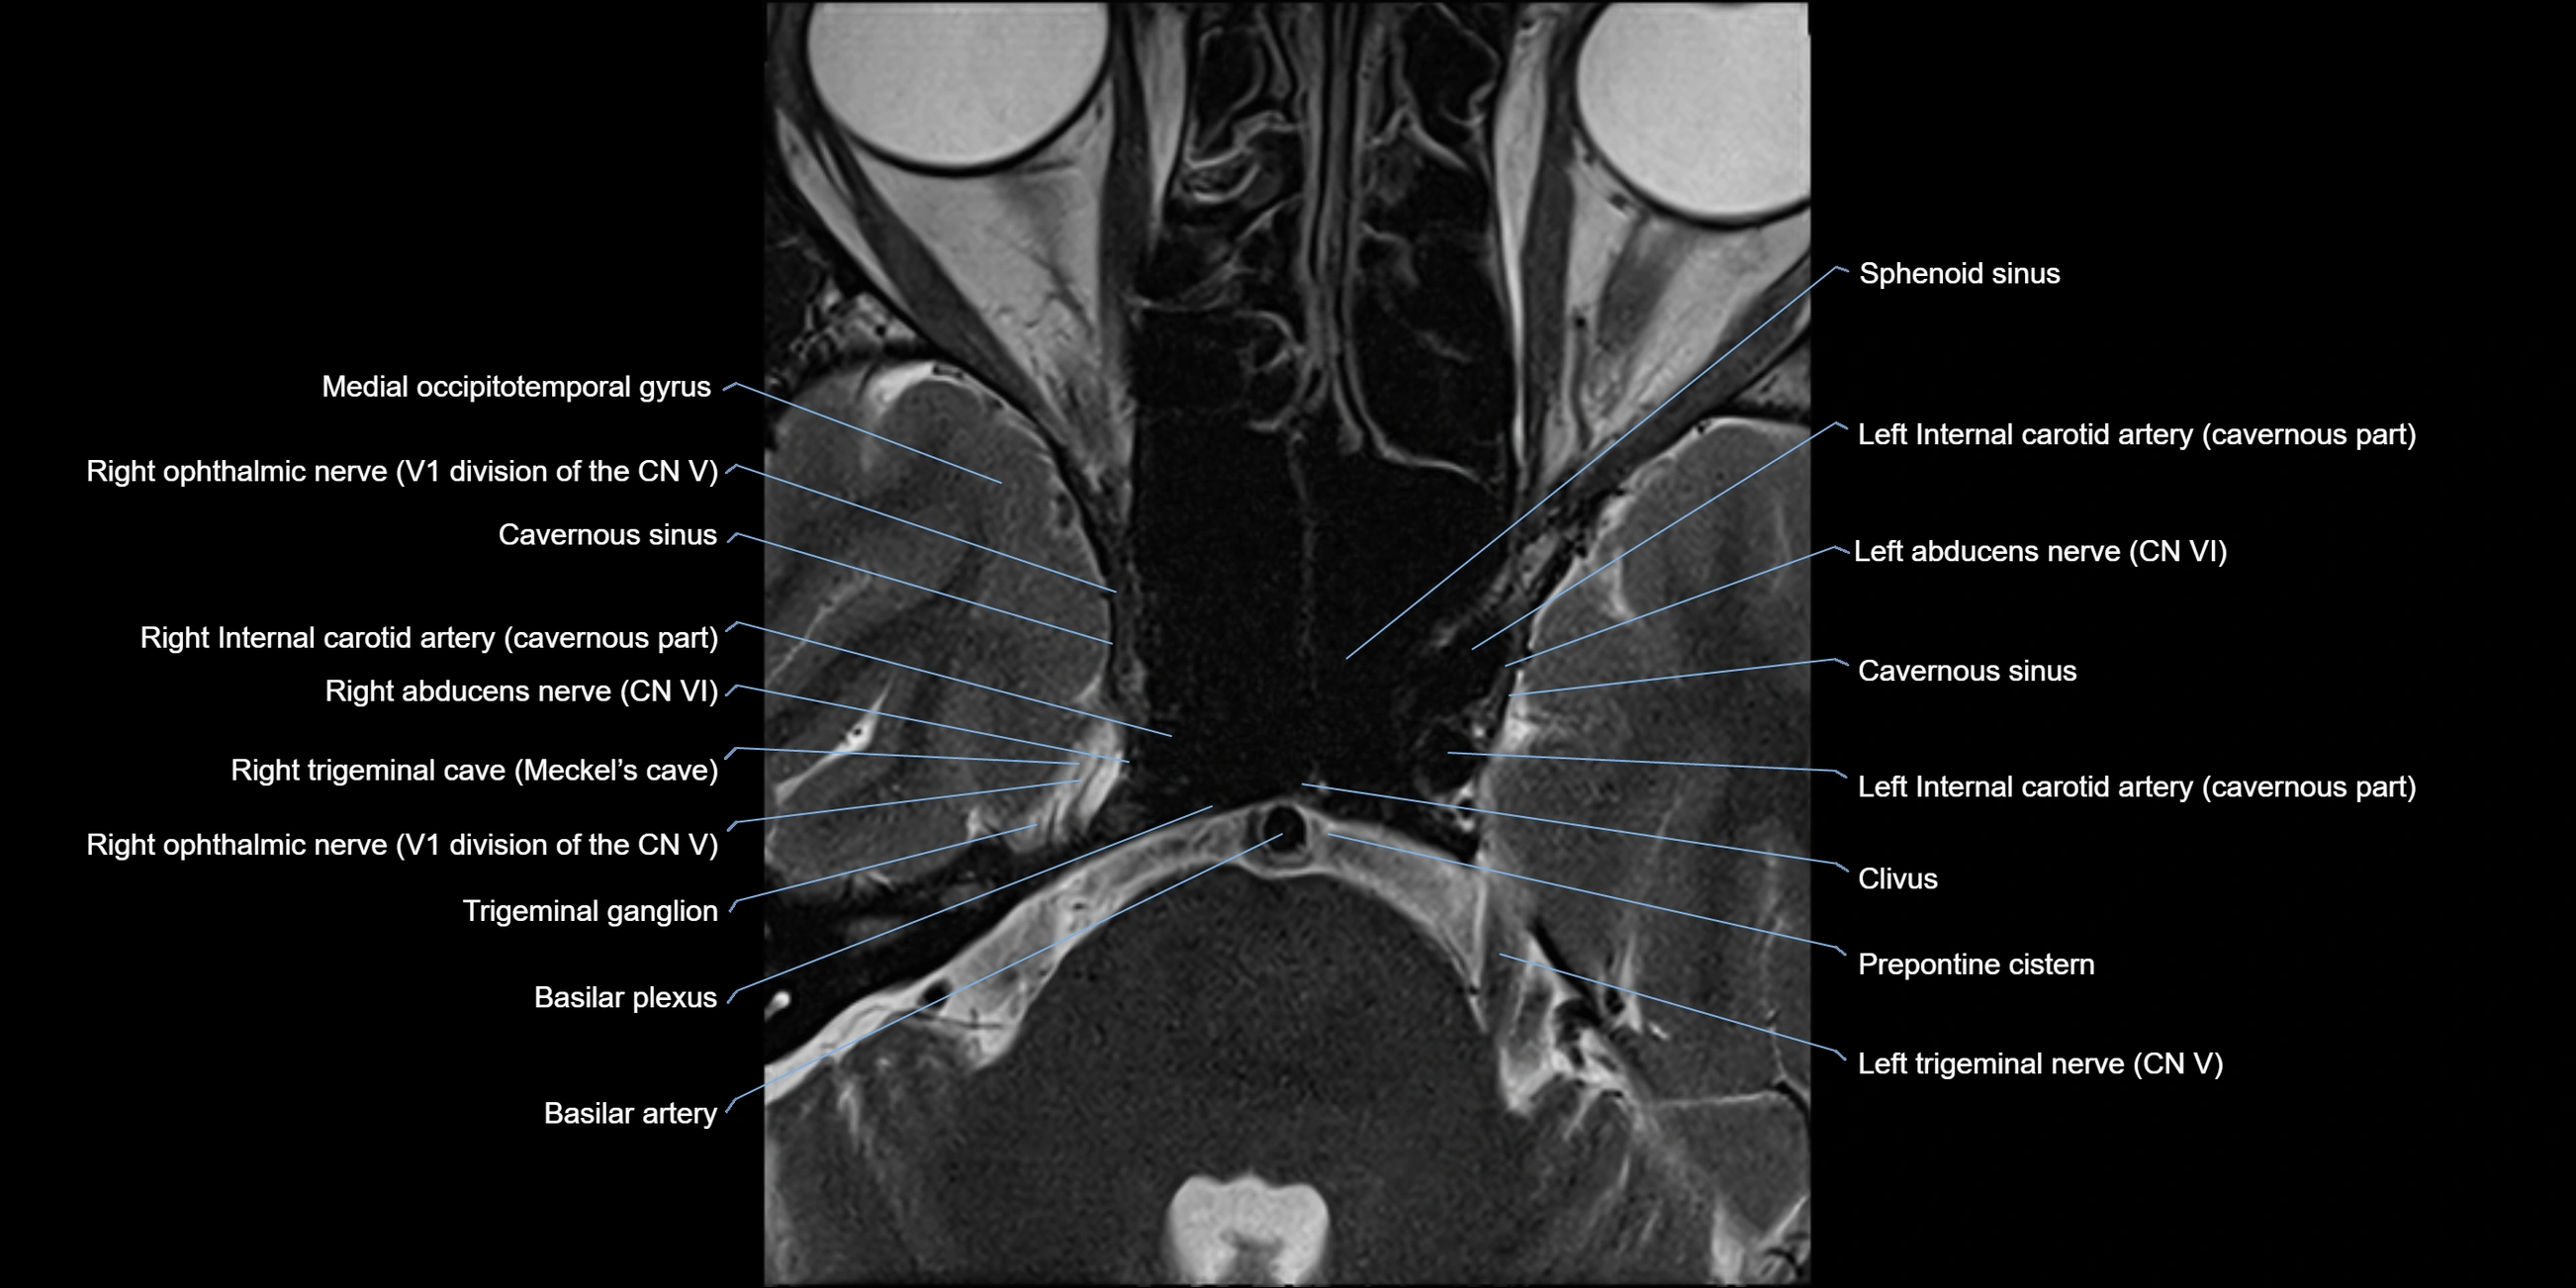

MRI Appearance

-

The abducens nerve is a small, thin, linear structure

Best visualized on high-resolution T2-weighted 3D MRI sequences (e.g., FIESTA or CISS)

Seen as a hypointense (dark) line running from the brainstem at the pontomedullary junction, traversing the prepontine cistern, and entering Dorello’s canal under the petrosphenoidal ligament, then into the cavernous sinus, and finally the orbit

May be challenging to visualize in standard MRI due to its small size

Pathology may be inferred by absence, displacement, or enhancement of the nerve

MRI images